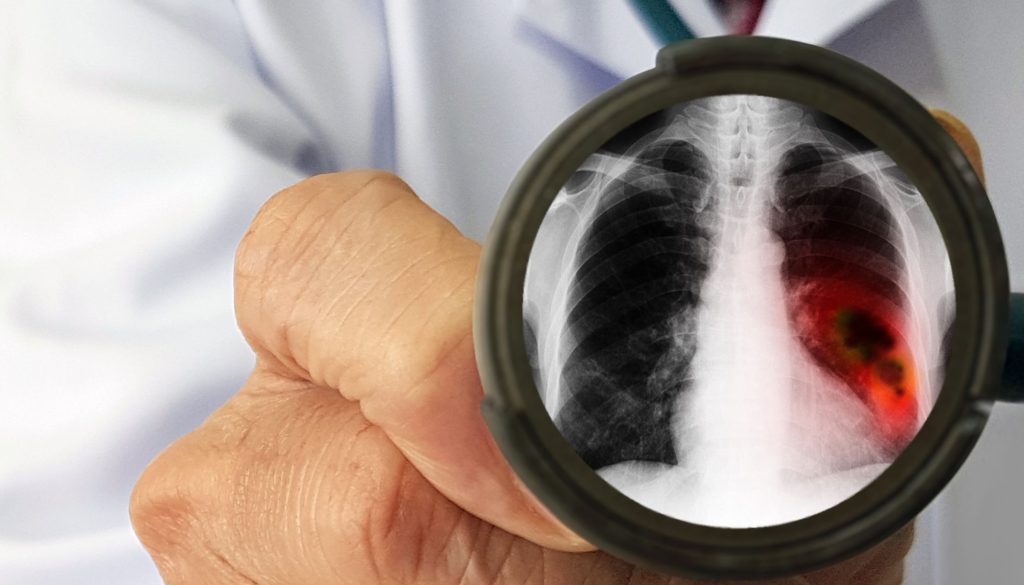

– **الأشعة السينية (X-ray):** تستخدم كخطوة أولى للكشف عن أي تغييرات غير طبيعية في الرئة.

– **التصوير المقطعي المحوسب (CT Scan):** يوفر صورًا أكثر تفصيلاً ويساعد في تحديد حجم الورم وموقعه بدقة.